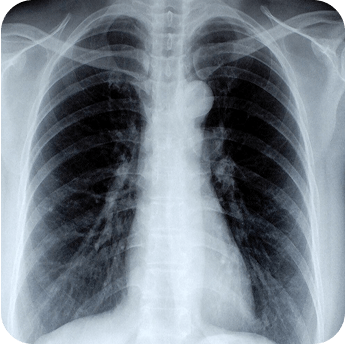

Определить болезнь можно с помощью рентгенографии или компьютерной томографии легких. На снимке будет видно, поражен ли орган.

Рентгенографическое исследование легких

С его помощью можно выявить новообразования и очаги воспалительных процессов.

Компьютерная томография

Данный метод также использует рентгеновское излучение, но позволяет получить более точное изображение исследуемой области «по слоям».